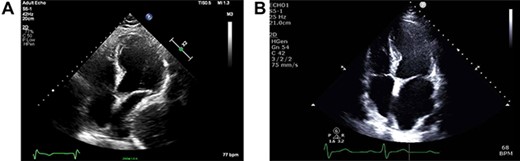

As part of the assessment, computed tomography (CT) coronary angiogram study was performed and it demonstrated a large fluid-filled oesophagus causing partial compression of the left atrium. Barium swallow (Fig. 1A and B), CT chest and abdomen (Fig. 2A and B) and transthoracic echocardiography (TTE) showed a 7.1-cm dilated oesophagus causing left atrial compression and a small hiatal hernia (Fig. 3).

(A) ECHO showing left atrial compression from megaoesophagus during diastole; (B) ECHO showing normal-sized left atrium 3 months after band removal.

Three months after band removal, the patient reported complete resolution of his symptoms. Repeat gastroscopy demonstrated oesophageal mucosal healing and no residual hiatal hernia. TTE showed that left atrium was moderately enlarged (but to a lesser extent compared to previous study) and normal left and right ventricular systolic function and dimensions with estimated left ventricular ejection fraction of 60%. Furthermore, the post-operative Barium swallow study (Fig. 4) demonstrated a 6.7-cm oesophageal dilatation and dysmotility. There was no significant delay in passage of barium into a non-distended stomach. Since band removal his weight had increased by 17 kg (112.8 kg, BMI: 36.4). Further discussions with the patient led to laparoscopic sleeve gastrectomy a month later (Fig. 5).

In the case of this patient, the extent of his megaesophagus resulted in significant compression of the left atrium observed on TTE and CT, which fortunately did not cause haemodynamic compromise or obvious and clinically evident intracardiac thrombus. To our knowledge, compression of the cardiac chambers by oesophageal dilatation is an extremely rare complication of LAGB. A systematic literature review of megaoesophagus in LAGB patients was performed (Table 1).